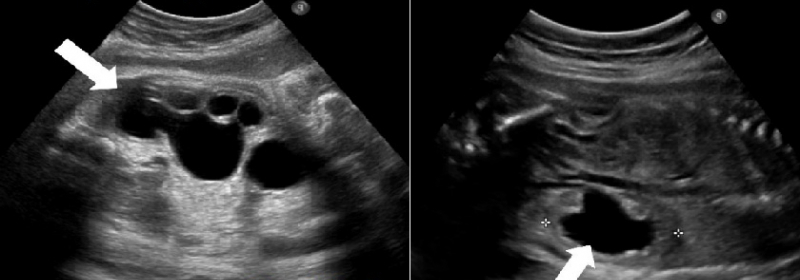

- ультразвуковое исследование почек;

Наиболее распространенными методами диагностики являются УЗИ и экскреторная урография.